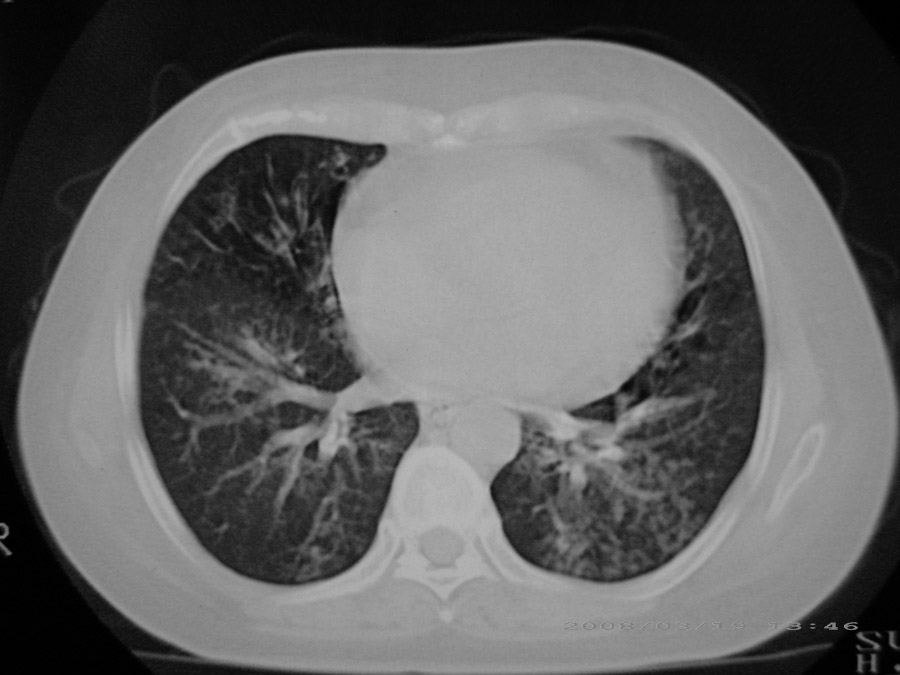

标题: CT13104:胸部大家看看啊,第一次发啊, [打印本页]

标题: CT13104:胸部大家看看啊,第一次发啊,

粟粒性结核

细支气管肺泡癌

本病例主要是癌性淋巴管炎与结节病的鉴别。好好查查吧。

密漫性沿纹理走行小结节影;有间质纤维化;可考虑尘肺;以图而论

血行播散性肺结核

双肺网状结构,小叶间质结节状增厚,考虑结节病

综合大家意见,结核、结节病、肺泡细胞癌均有可能,间质性肺炎暂不考虑,病灶纠集不明显,纵隔未见钙化淋巴结,尘肺可能性不大,但还是要密切结合临床诊断。

今天重新仔细看了看,矽肺确实不能除外,病灶主要表现为间质结节及纤维化。好好问问病史吧。